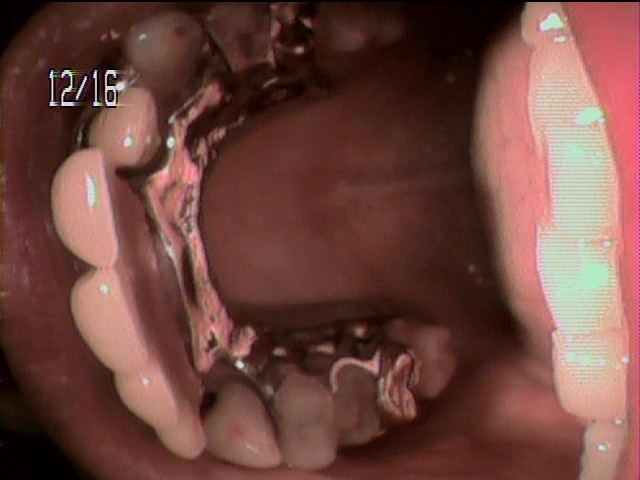

本日、出来上がりました自費の部分入れ歯ー下顎メタルプレートの症例です。

81歳の女性OUさんはとけも若々しいかたで、上下ともに、ぶぶん入れ歯ですが、今回は下顎の左右の奥歯のメタルプレートの入れ歯を新しく作りました。

自費によるメタルプレート義歯で、薄く丈夫な義歯として、とても舌感の良好な状態にすることができ、さらに自由な義歯の設計ができるため、残っているはにかける針金は白金加金で作成し、残存歯にやさしい設計となっており、舌に触れるバー部分はコバルトクロム合金で、丈夫に薄く作ってあります。

(参考代金;30万円)